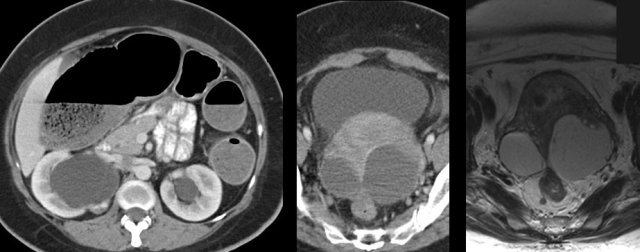

DIE is a potentially devastating, gynaecological condition.

By repeated episodes of bleeding, resorption and the resulting formation of scar tissue, the endometriotic implants may cause pain, dyspareunia and subfertility.

DIE, if localized in Douglas pouch and the vesico-uterine recess, may aggressively invade the rectum, bladder and ureters, with all its sequelae, as colonic obstruction, micturition problems and hydronephrosis.

In prominent, longstanding DIE, the resulting bulky scar tissue of DIE (*), may cause narrowing, and eventually total obstruction, of the colonic lumen.

In this young lady with unexplained chronic abdominal symptoms for many years, CT and subsequent MRI demonstrated extensive endometriosis.

In addition there are large, adhesive endometriotic cysts (“kissing ovaries”),   bilateral hydronephrosis and complete obstruction of the colon, due to ingrowth of endometriosis in the ureters and the rectum.